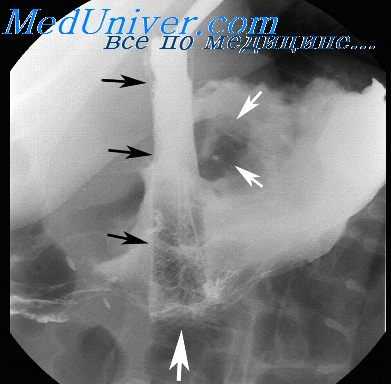

При обзорной рентгенографии грудной клетки и брюшной полости выявляется скопление газа в средостении (пневмомедиастинум) и параэзофагеальном пространстве, гидропневмоторакс. Проведение рентгенографии пищевода с водорастворимым контрастом позволяет увидеть выход вещества за пределы эзофагеальной стенки и уточнить место разрыва пищевода. В сомнительных случаях выполняется фарингоскопия, эзофагоскопия, медиастиноскопия.

Деструкция стенки пищевода, вызванная эрозивным (коррозивным) или язвенным процессом, при рентгенологическом исследовании проявляется прямым симптомом — депо бария или нишей. Язвенная ниша имеет конусовидную или неправильную форму. Длинник ее расположен перпендикулярно контуру пищевода, размер колеблется от 0,2—0,3 до 0,6—0,8 см.

В краеобразующем положении она выступает за пределы внутреннего контура пищевода. При этом воспалительный вал у ее основания иногда обусловливает своеобразную краевую деформацию стенки пищевода, имеющую вид цифры 3. Хроническое течение воспалительно-деструктивного процесса в пищеводе сопровождается конвергенцией складок слизистой оболочки к нише, эзофагитом, сужением и деформацией (укорочением) органа.

Изъязвления пищевода часто (до 50%) сочетаются с аналогичным процессом в желудке или двенадцатиперстной кишке, а также с грыжами пищеводного отверстия диафрагмы. Язвенную нишу пищевода необходимо дифференцировать от скопления (депо) бария в кратере распадающейся опухоли, в небольшом дивертикуле и деформированных или изъязвленных участках стенки, появившихся на почве бывшего ожога, инородного тела, периэзофагита или варикозного расширения вен.